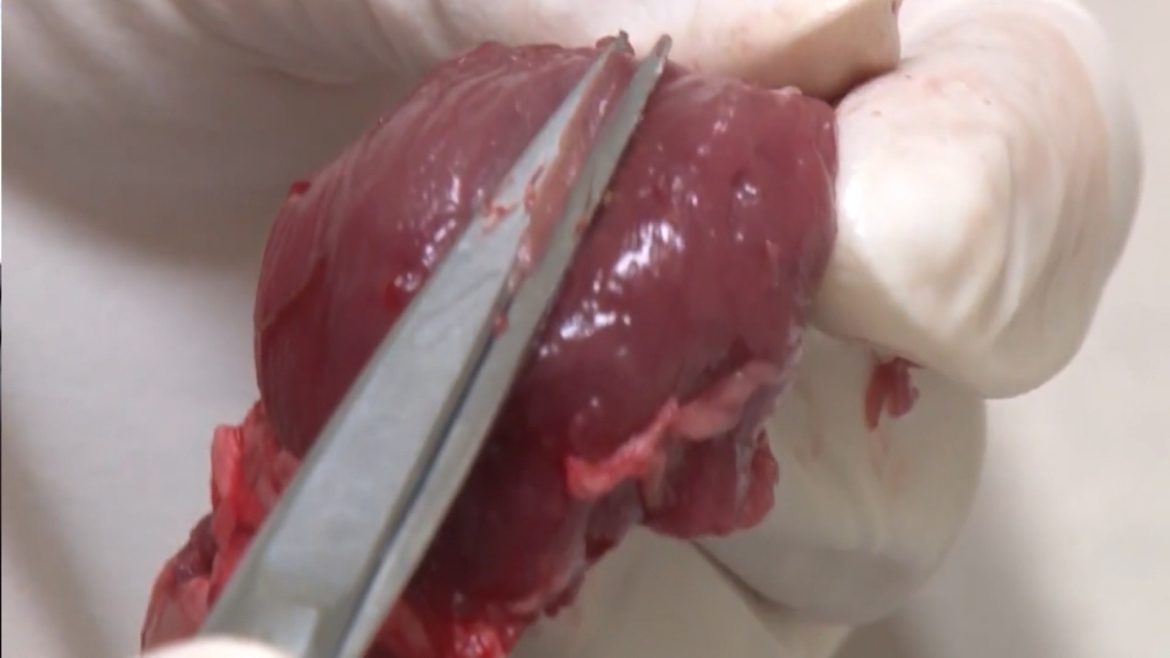

Најбоља заштита људи и животиња свакако је превентива. Болест се спречава строгим ветеринарским надзором. Зато се свима препоручује да поштују прописе и носе узорке меса на преглед. Најбоље је донети дијафрагму, односно „круну“ дијафрагме.

„Најзначајнија мера је преглед меса. Узима се круна дијафрагме, са обе стране. Ако се коље више свиња, узорак се узима од сваке. Чешће су заражене старије свиње, али и прасад могу бити носиоци. Ризику су изложене свиње које се пуштају на пашњак. Док се не добију резултати, не сме се јести недовољно печено месо или пробати сирове смесе за кобасице. Термичка обрада мора бити на температури изнад 70°C и довољно дуга*,“ истиче др Дмитрић.